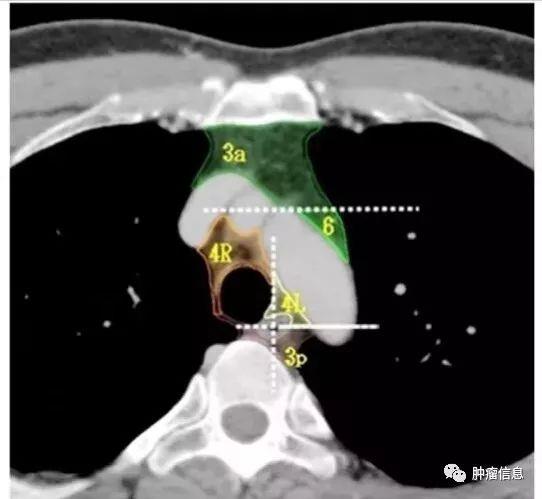

第3组淋巴结分为3a和3p:3a:前部的血管前淋巴结上界:胸膜顶下界:隆突水平前界:胸骨后后界:上腔静脉前缘3p:后部的气管后淋巴结上界:胸膜顶下界:隆突水平

4R:右侧下气管旁,自无名静脉与气管交界区至奇静脉,自气管右侧至气管左侧缘。上界:无名静脉与气管交叉处下缘下界:奇静脉下缘4L:左侧下气管旁,自主动脉弓上缘至左侧主肺动脉上缘,气管左侧缘以左。上界:主动脉弓上缘下界:左肺动脉干上缘气管左侧的矢状面是4L与4R分界线。

主动脉旁淋巴结:位于升主动脉,主动脉弓的前面和两侧,迷走神经前面。上界:主动脉弓上缘切线下界:主动脉弓下缘